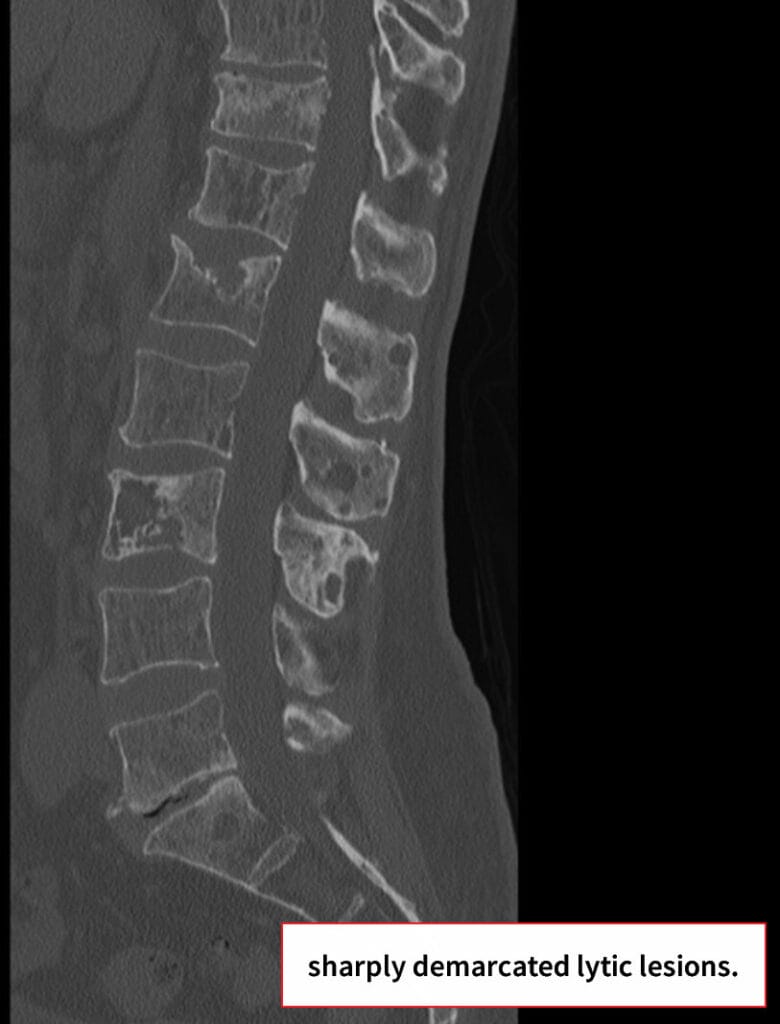

영상 소견

단순 방사선(X-ray) 소견

🟦 다발성 둥근 저음영 병변 (punched-out lesions)

두개골, 장골, 늑골 등에서 테두리가 뚜렷한 원형 결손이 관찰됩니다.

🟦 Diffuse osteopenia

광범위한 뼈 감소 소견으로 병적 골절 위험이 증가합니다.

CT 소견

🟦 골소실 및 골파괴 병변

X-ray에서 보이지 않던 작은 병변도 확인할 수 있으며, cortical disruption이나 골절을 평가하는 데 유용합니다.